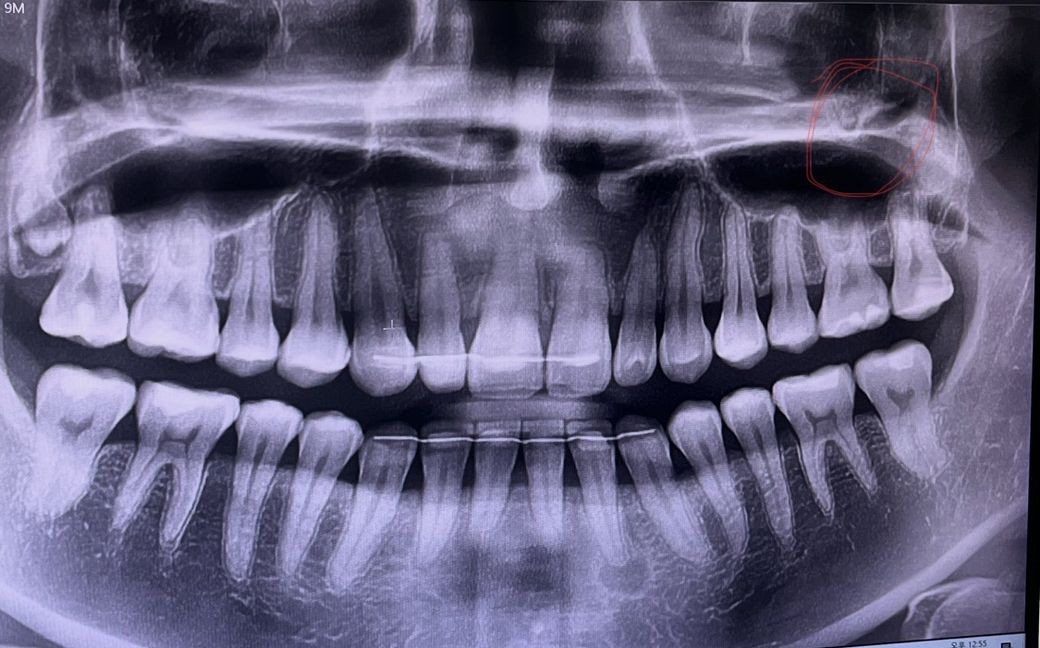

안녕하세요. 여러 치과나 이비인후과에서는 이상이 없다고 하는데 왼쪽 입천장 부위(어금니 잇몸 옆쪽으로 튀어나온 뼈 부분)에서만 느껴지는 구취가 너무 스트레스입니다. 음식을 먹으면 왼쪽 입천장이 꽉 막혀서 답답한 느낌과 함께 이물감도 느껴지고 유독 그 부위만 음식물 냄새와 알 수 없는 무언가가 섞여 악취가 납니다. 양치를 하고 나서도 바로 해당 부위에서만 안좋은 치약냄새가 나구요. 혀로 튀어나온 뼈 부분을 막으면 구취가 전혀 느껴지지 않습니다. 엑스레이 상 비교해봤을 때 동그라미 친 부분이 뚫려있는 것 같은데 혹시 관련이 있을까요? 상악동이나 다른 이상있는 부위가 있는지 문의드립니다. (편도는 제거한 상태라 편도결석 문제는 아닙니다ㅜㅜ)

상악동에 문제가 잇거나 그렇진 않습니다. 치과에 가셔서 일단 스켈링 및 잇몸치료를 받아보시고 오히려 치아는 사진상으로 오른쪽 아래 치아 뿌리끝에 염증이 잇는것처럼 보입니다.

1. 엑스레이상 특별한 문제는 없어보입니다

2. 표시된 부위는 상악동 하벽이 아닙니다 혀로 훑어서 느낄 수가 없습니다

3. 상악동 부위도 딱히 염증소견 없습니다